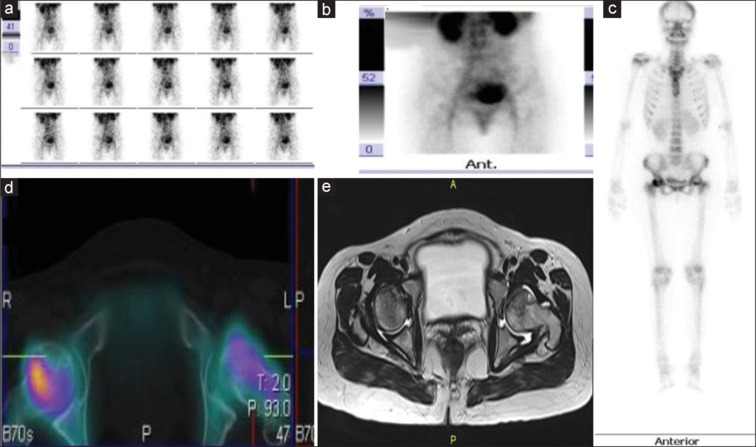

目的:骨显像是一种评价疑似骨坏死患者的灵敏成像方法。我们评估了骨单光子发射计算机断层扫描/计算机断层扫描(SPECT/CT) (CBS)对已知风湿病或其他结缔组织疾病和临床怀疑骨坏死患者的诊断性能,并与磁共振成像(MRI)进行了比较。方法:这项前瞻性诊断准确性研究纳入了70例临床怀疑骨坏死的患者,他们接受了平面三期骨扫描以及区域SPECT/CT (CBS)和区域MRI。MRI被认为是诊断CBS的敏感性、特异性、预测值和准确性的标准。科恩的kappa统计也计算了协议。结果:根据疑似骨坏死的关节部位分布:髋关节21例,膝关节43例,踝关节6例。70例患者中有30例MRI检出骨坏死。CBS的敏感性为100%(检测到30/70),特异性为97%(假阳性2/40)。总的来说,两次扫描对于骨坏死的诊断有很好的一致性(Cohen’s kappa统计值= 0.94)。除了可疑部位外,CBS在13例患者的19个其他无症状部位检测到骨坏死。结论:本研究表明,包括全身成像和SPECT/CT在内的CBS在检测骨坏死方面具有高度敏感性,其准确性与局部MRI相当。其固有的全身成像技术可以检测多灶性骨坏死。它可以作为常规x线平片后的早期检查方式来确定诊断。

Results: The distribution of the patients based on the joint regions suspected to have osteonecrosis is as follows: 21 hip, 43 knee, and six ankle. MRI detected osteonecrosis in 30/70 patients. CBS had a sensitivity of 100% (30/70 were detected) and a specificity of 97% (2/40 were false positive). Overall, there was good agreement between the two scans regarding the diagnosis of osteonecrosis (Cohen's kappa statistic = 0.94). In addition to the suspected sites, CBS detected osteonecrosis in 19 additional asymptomatic sites in 13 patients.